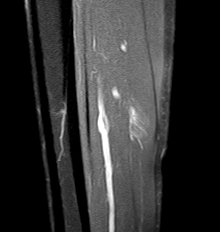

MRI

Grade 2b lateral soleus